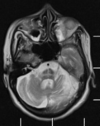

Qual o padrão da imagem na AMS-C?

Atrofia de cerebelo (vermis) e tronco (principalmente ponte); Hipersinal T2 na ponte: Sinal da cruz na ponte (não patognomônico), perda da barriguinha da ponte, Hipersinal nos pedúnculos cerebelares médios;

149

Atrofia de múltiplos sistemas tipo C

Atrofia da ponte e dos pedúnculos cerebelares médios Atrofia de múltiplos sistemas